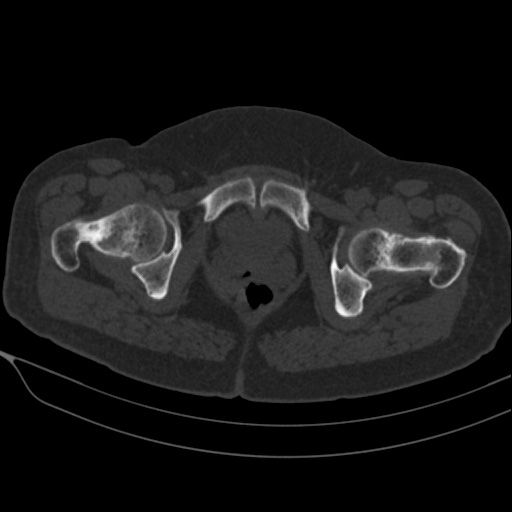

Dev Hücreli Kemik Tümörü

Kemiğin selim-agresif tümörü olarak kabul edilir. Genç erişkinde osteolitik karakterde kemik tümörüdür. Uzun kemiklerin ekleme yakın uç kısmından çıkabilir. Hastalar tümör bölgesinde devamlı ve giderek artan inatçı bir ağrı ve şişlik ile başvururlar.Sadece küretaj yapılan hastalarda yüksek lokal nüks yanında akciğer metastazı yapma potansiyeli olduğundan lokal agresif tümör olarak kabul edilir. Ama bu metastazlar ölümcül değildir.Diz eklemi en sık tutulan bölgedir. Diğer sık tutulan bölge el bileğidir. Kemik korteksini harap ederek yumuşak dokulara yayılım gösterebilir. Tanı için biyopsi şarttır. Brown tümörü ile ayırıcı tanısı yapılmalıdır. Tanı esnasında akciğer tomografisi çekilmelidir.

Tedavide genişletilmiş küretaj ve adjuvan ajanlarla kalan tümör hücreleri öldürülmeye çalışılır. Adjuvan ajan olarak; sıvı azot, alkol, fenol, argon koter, kriyoterapi, yüksek hızlı burr ve sementleme (kemik çimentosu) uygulanır. Eklemin tutulduğu vakalarda eklem feda edilir,protez veya artrodez uygulanabilir. Rezeksiyonun zor olduğu olgularda denosumab kullanılması önerilmektedir.Hastaların lokal nüks ihtimaline karşı 10 yıl süre ile takibi yapılmalıdır.